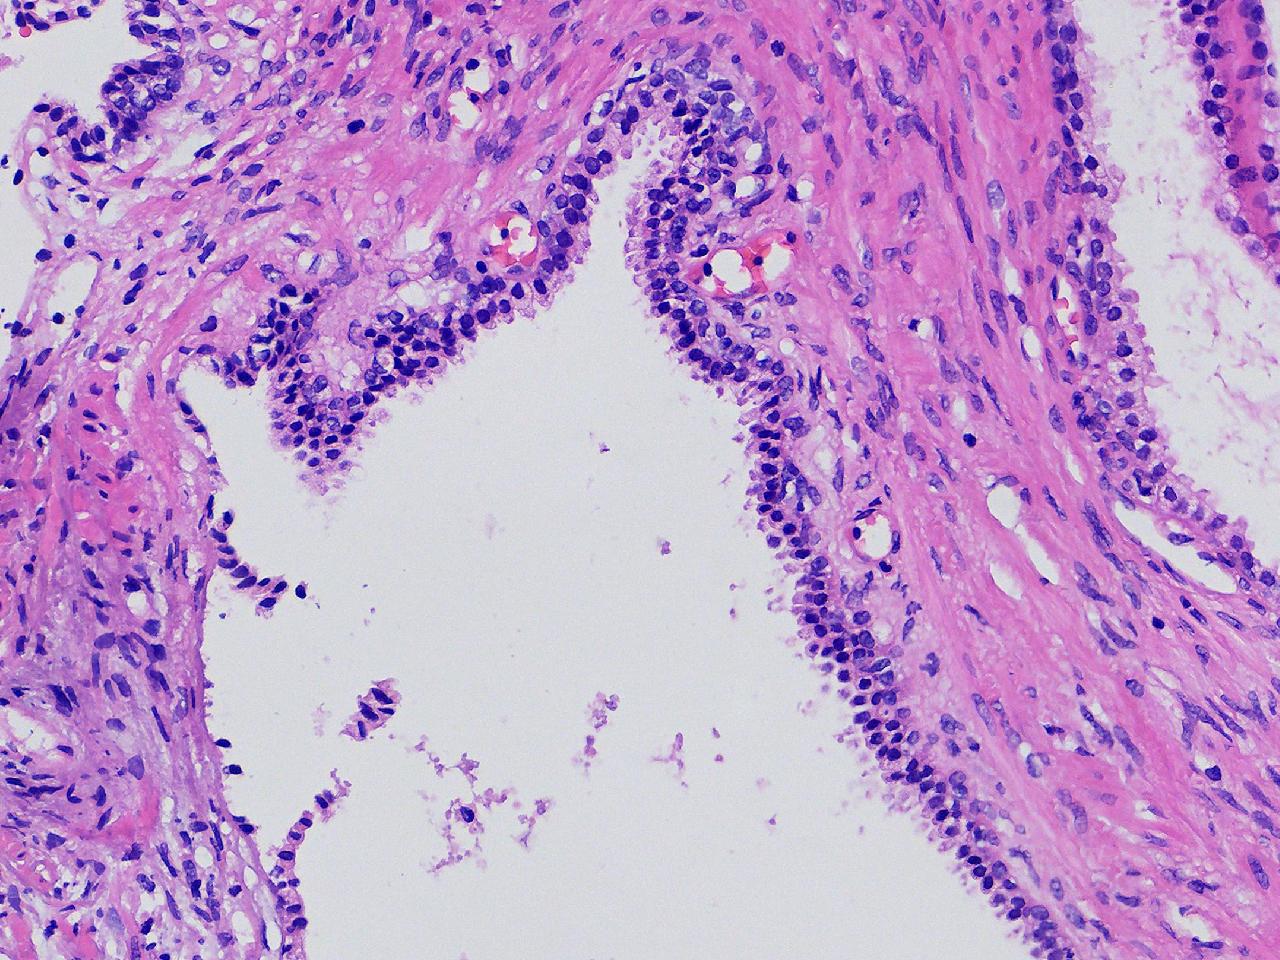

男,68岁,前列腺电切标本。

前列腺电切标本

灰粉色条索状软组织多块,5X4X3厘米。

前列腺增生。

BPH.